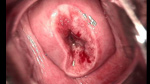

• CIN 2-3 leep術(shù)后CIN 2-3 leep術(shù)后

• CIN 2-3 修復(fù)后CIN 2-3 修復(fù)后